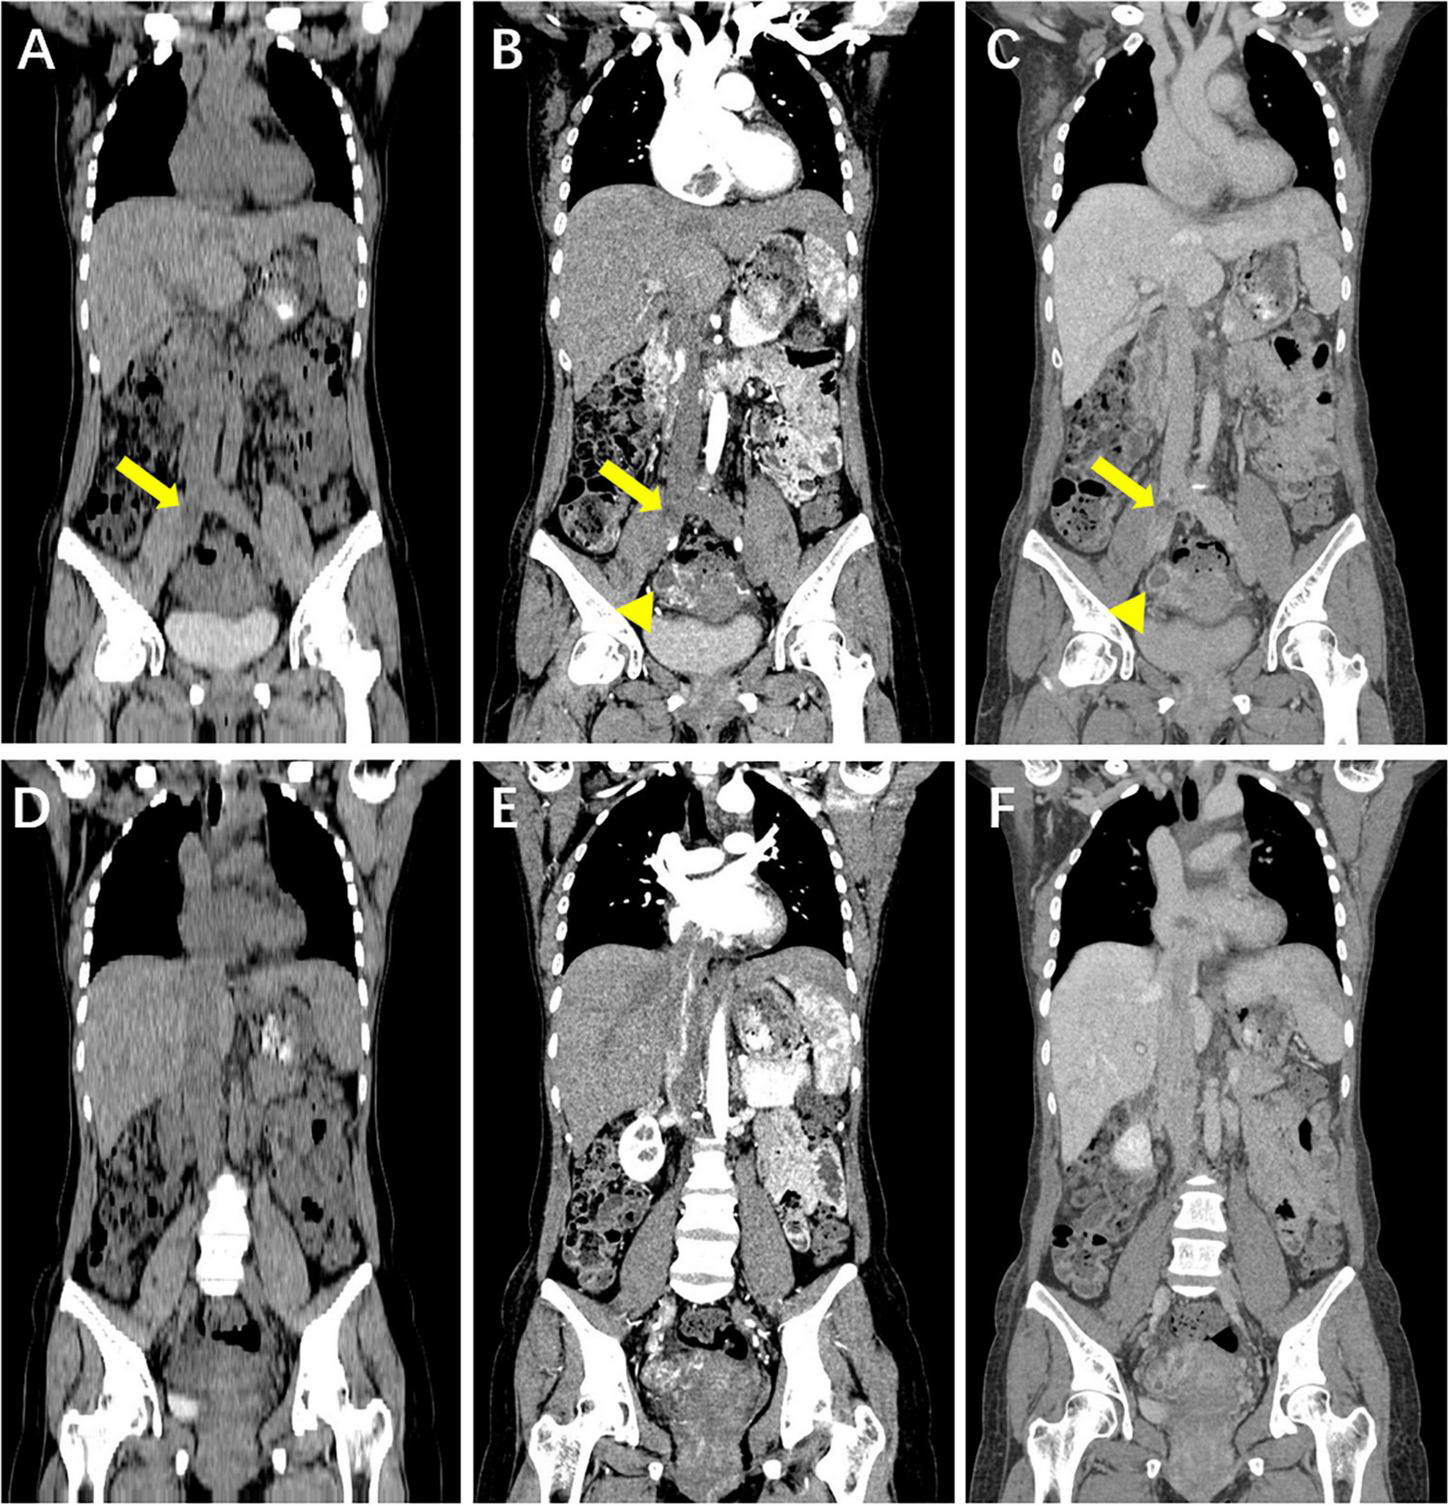

FIGURE 1

Coronal reformatted computed tomography (CT) image of the chest, abdomen and pelvis. (A–F) Hypoattenuating filling defect located within the right iliac veins across the inferior vena cava (IVC) into the right atrium. Contrast-enhanced CT images show that intravenous lesions demonstrated mainly moderate progressive enhancement, with localized non-enhancing necrotic areas (arrow). A circular enhanced thick-walled cystic lesion at the right of the uterine body is incidentally noted (arrowhead). (A,D) Unenhanced phase image. (B,E) Arterial phase of contrast enhancement image. (C,F) Portal phase of contrast enhancement image.